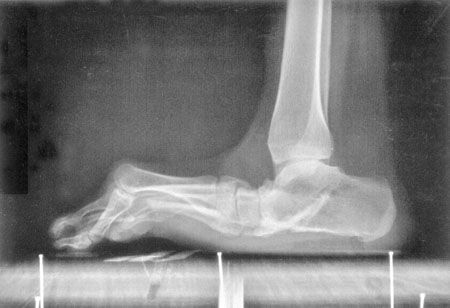

Mise au point L'hallux flexus avec metatarsus elevatus de l'adulte , Henri Mestdagh CHU de Lille, Lille, France N°142 - Mars 2005 ● 7 min de lecture